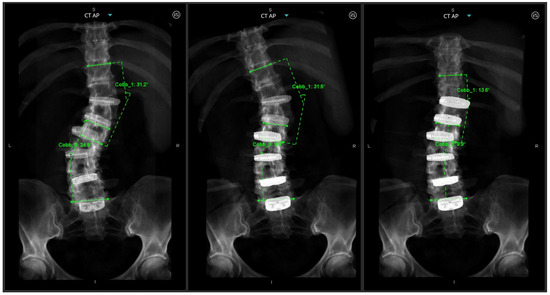

Figure 7. (A) (left) Preoperative AP X-ray; (middle) intraoperative AP long film showing appropriate coronal correction; (right) postoperative standing AP X-ray. (B) (left) Preoperative robotic plan with patient-specific rod geometry; (middle) intraoperative sagittal long film with appropriate sagittal correction; (right) postoperative standing lateral X-ray.

An intraoperative CT scan with a navigation frame attached to the patient is then obtained as a confirmation scan and to allow for navigated repositioning of any screws that are needed. A navigated burr is then used through the existing transfascial or percutaneous incisions to decorticate and drill out all facet joint levels that do not have anterior interbody fusions. These decorticated pockets are then packed with the bone graft of choice for the surgery. If needed, a mini-open exposure is performed for posterior column osteotomies (PCOs) to allow for further lordosis or scoliosis curve correction. Rods are then passed using a minimally invasive technique with rod passage inserters. While this historically has carried the possibility of great difficulty, the enabling technologies of planar screw planning has allowed this to proceed in very routine fashion. Satellite rods are first secured and locked into position so that their minimally invasive towers can be removed from the working airspace over the wound and any distractive techniques are completed if they are functional kickstand rods [16]. Placement of both main rods then follows. Acceptable alignment is then confirmed using a long film or a series of stitched X-rays (Figure 7). Closure proceeds in the usual fashion after all set screws are secured and towers removed.

Mean improvement in spinopelvic alignment were sagittal vertical axis (SVA) −5.2 cm (range −20.3 to 4.5 cm), pelvic tilt (PT) 10.8° (range 1–23°), and pelvic incidence–lumbar lordosis (PI-LL) mismatch 21.9° (range −5° to 47°). Eight patients with scoliosis showed improvements in their coronal Cobb angles of 27.3° (range 19–43°). Ten patients ambulated within the first 2 postoperative days. The mean LOS was 5.8 days (range 4–10) and there were no ICU admissions.

This is an important adjunct to patient selection and operative planning, as the inclusion of these tools may increase the pool of patients in which MIS deformity correction may be considered. More recent reports have shown that in cases of even marked deformity, MIS techniques have shown to be quite effective while still benefiting from reduced complication profiles [23]. While these data may indicate that MIS approaches are feasible to correct ASD, they may not underscore the intraoperative limitations and challenges of applying such an approach. Anticipation of the challenges to applying MIS in ASD correction, such as tower collision, fixation of satellite rods, subfascial passage of rods, etc., is imperative for bringing these techniques into regular practice. Our report therefore advocates for preoperative planning of MIS constructs using robotic software to design these constructs in three-dimensional space, but also to modify screw and rod trajectories as intraoperative collisions and conflicts are anticipated. For example, Figure 7 illustrates a case in which two right-sided pedicle screws are preoperatively selected to affix to a satellite rod, rather than the main rod, with pre-adjusted trajectories of these screws allowing for easy intraoperative passage of right-sided rods. Loading pre-planned screw trajectories into the surgical robot ensures accurate and streamlined transfascial placement, accounting for previous components of the case during Stage 1 when interbody cages are placed. Also illustrated in Figure 7 is the omission of a of the left L5 pedicle screw, to avoid tower collision when lordosis correction is achieved. Tower collision at the lumbosacral junction is a common spatial limitation in the operative workspace and may be difficult to anticipate as lordosis correction is achieved during open surgery. This demonstrates how preoperative planning software may aid in anticipating intraoperative spatial limitations of the workflow and permits adjustments of the construct design to yield a surgical plan which achieves an optimal surgical correction but is also technically feasible through an MIS approach. Prior studies showing use of robotics in adult spinal deformity have mostly relied on accuracy of screws or placement of S2-alar-iliac pelvic fixation, which highlights the need to expand upon the benefits of robotics use specifically during this planning stage [24].

Our cohort’s final radiographic parameters show the successful realignment of sagittal parameters as an endpoint even in cases of marked sagittal imbalance (patient 6, SVA 21.0 cm; patient 12, SVA 20.4 cm) and mean improvement in coronal Cobb measurements of 27.3° for patients with degenerative scoliosis, highlighting the success of MIS techniques in appropriately selected patients. While the success of open spinal deformity is well established [17,18,19], complication profiles can differ, and prior studies have demonstrated the benefits of minimally invasive approaches to reduce intraoperative and postoperative complications and hospital stay lengths [22]. Of note, there were no wound, neurologic, or implant-related complications in our series, which is consistent with these prior studies. Here, we achieved optimal radiographic correction outcomes, with similar complication profiles to that of the open literature. Again, these results emphasize that careful preoperative construct planning in select patients allows for comparable outcomes in ASD correction through an MIS approach when compared to open robotic-assisted techniques.